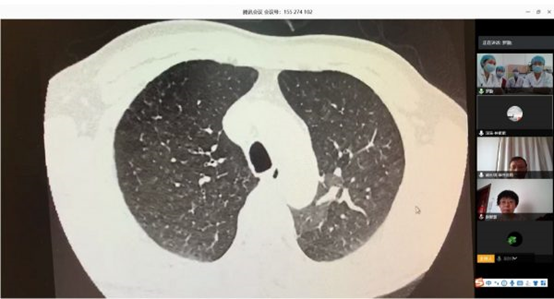

阜外医院肺血管病房充分利用“互联网+医疗”的优势作用 开展远程线上查房